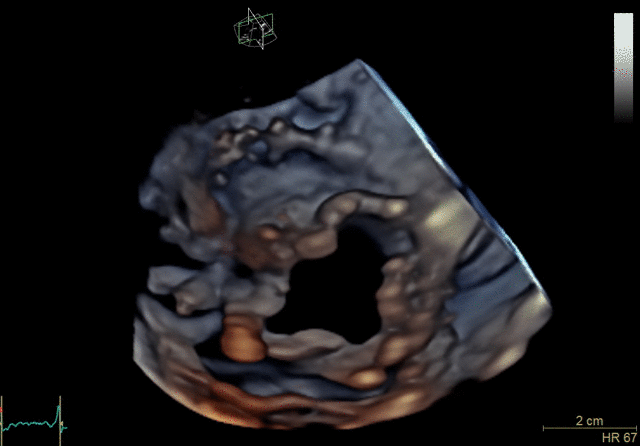

4D Auto MVQ*

4D Auto AVQ*